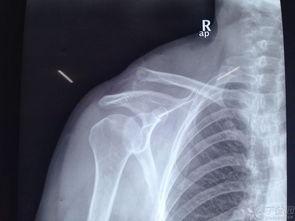

看我的肩膀,都脱臼了呀,揭秘肩部损伤的严重后果

那天,我正沉浸在办公室的忙碌中,突然,一阵强烈的疼痛从肩膀袭来。我下意识地摸了摸肩膀,我的肩膀竟然脱臼了!这可真是让人措手不及啊。我赶紧站起来,试图活动一下肩膀,但疼痛感愈发强烈,仿佛有一把无形的刀在肩头划过。

疼痛升级:肩部脱臼的瞬间

就在我试图活动肩膀的时候,疼痛感瞬间升级。我感觉到肩膀的关节处传来一阵刺痛,仿佛有什么东西在撕裂我的肌肉。我忍不住倒吸一口凉气,心想:“这肩膀,怎么这么脆弱啊?”

我赶紧找来同事帮忙,他们帮我轻轻地将肩膀复位。那一刻,我仿佛听到了一声清脆的“咔哒”声,肩膀似乎又回到了原来的位置。但疼痛并没有因此减轻,反而更加剧烈。